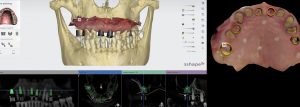

TIP: The accuracy of image registration between the CBCT and IOS scans can be improved with radiographic markers (composite blobs). Removing sources of radiographic scatter (in this case, the PFM bridge) also improves the accuracy. Fig. 3

The use of radiographic reference markers: a composite such as G-ænial Universal Injectable with a radiopacity of 250% Al, does not result in radiographic scattering during CBCT scans.

Prior removal of the porcelain-fused-to-metal (PFM) bridge: reduction of radiographic scatter caused by the metallic components of the prosthesis Intraoral surface scans (IOS) before and after removal of the original PFM bridge superimposed on the CBCT scan: this facilitates the planning of implant placement from a restorative perspective (restoration driven implant placement). (3Shape Implant Studio software) Fig. 4 (i, ii)

Planning of implant placement. A surgical guide is designed based on the desired implant position. (3Shape Implant Studio software) Fig. 5